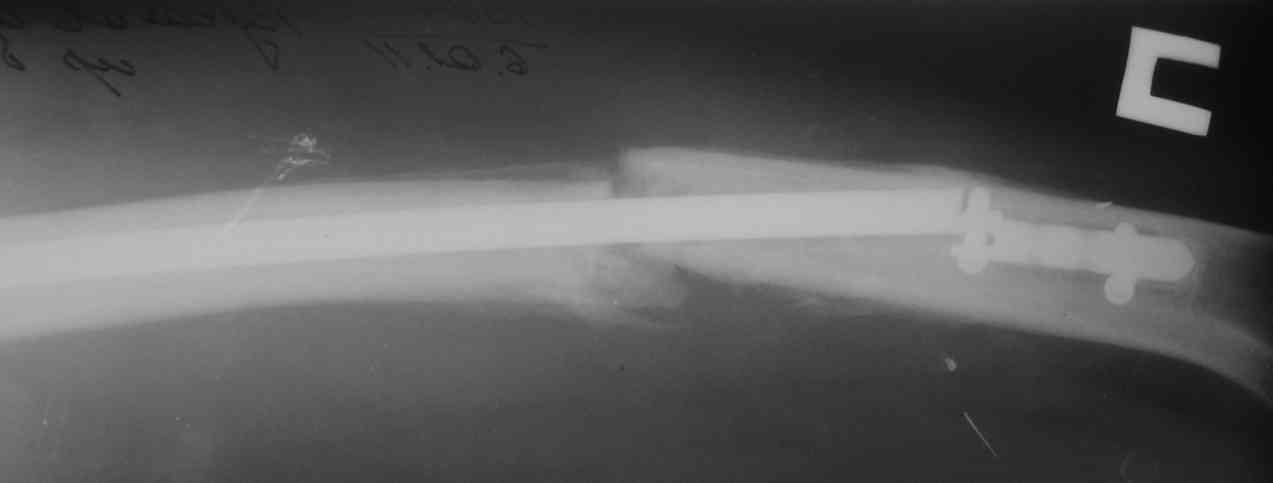

Одной рентгенограммы недостаточно, чтобы планировать подобную операцию. Вот похожий случай, который пришлось оперировать 3 мес. назад. Тоже короткий гвоздь. Шляпки винтов проксимального фрагмента полностью погружены в костную ткань, чего уже достаточно для необходимости обнажения этой зоны. У этого же больного оказались полностью разрушены шлицы 2-х дистальных винтов, так что и там нужно было "открываться".